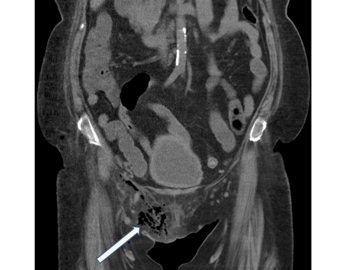

【112-2 醫學(五) 第73題】糖尿病病患主訴會陰部紅腫脹痛,血液中白血球數目增加,電腦斷層檢查呈現如圖。箭號所指之異常最可能之初診斷為下列何者?

詳解

破題關鍵

糖尿病患者出現會陰部紅腫脹痛、白血球升高,加上電腦斷層(CT)影像顯示會陰部軟組織內有大量氣體(箭號所指的黑色不規則區域),這些都是壞死性筋膜炎,特別是佛尼爾氏壞疽(Fournier's gangrene)的典型表現。